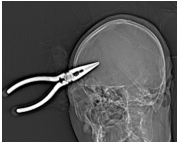

患者头部CT显示钳子穿破颅骨插入脑内近5cm深,周围脑组织有少量出血,一般遇到此种情况,选择的手术方案都是全身麻醉下进行局部切开后拔除钳子,再进行深入的清创止血手术,但这样会对脑部造成二次损伤,颅内损伤面积增大,会导致手术后患者留下严重的后遗症,甚至危及生命。

江峰主任反复阅片并组织科室进行疑难病例术前讨论,认为所幸患者颅内大血管并未伤及,损伤的脑组织位于右侧大脑半球亚功能区,故患者神志仍然清楚,目前无明显神经功能障碍。

手术中拔除的钳子和术后脑部CT

术后患者步行出院

本次特殊病例的救治,由江峰主任带领颅脑外科医师团队在急诊科、麻醉科、影像科等多学科的密切配合下,反应迅速、判断果断准确,采用最佳的手术方案,成功救治了这一罕见病例,为患者量身订造的“拆弹”方案,既为患者解除了危险,也为患者节省了治疗费用,患者及家属对我院颅脑外科医生的医术及医德医风均竖起了称赞的大拇指。